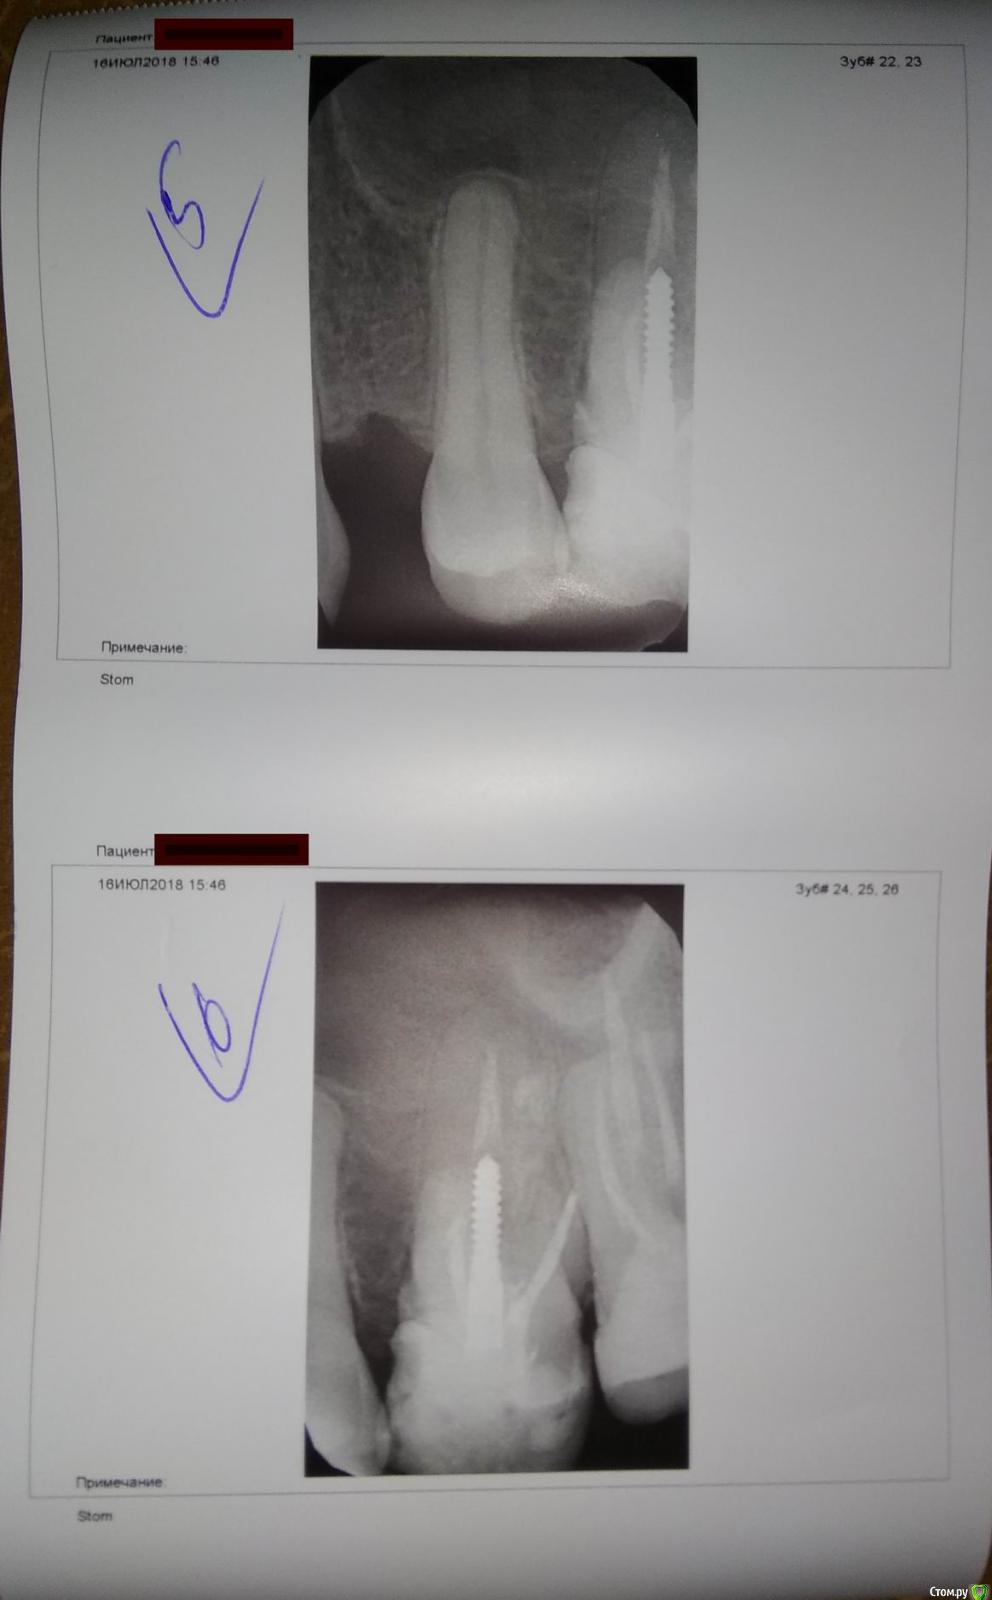

Остро заболел шестой зуб на верхней челюсти, в районе корня. Десна немного распухла.

Сделали снимки радиовизиографом - терапевт сказал, что вроде для него работы нет.

И по результату КТ - направили к хирургу на удаление 6 и 7 зубов...

Хирург говорит - удалять шестой.

Можно и нужно ли пытаться его вылечить без удаления?

post-55588-0-13418000-1532456619_thumb.jpgpost-55588-0-34704800-1532456739_thumb.jpgpost-55588-0-69223700-1532456746_thumb.jpgpost-55588-0-37543000-1532456752_thumb.jpg